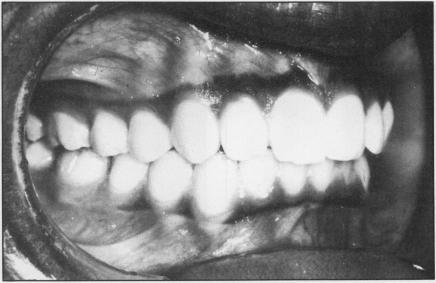

The authors of this article offer an introduction to the field of orthodontics. They present the latest advances in orthodontic appliances and some of the possible consequences of orthodontic treatment. They discuss a number of cases and offer examples of some of the more common problems that the orthodontist is asked to treat. Such cases include severe Class II, division 1 malocclusion, surgical orthodontics, "long-face" syndrome, adult orthodontics-TMJ-periodontics, late adult growth, and post-retention changes. Practical information useful to the physician who encounters patient with these disorders is balanced with good research data to support the various claims.

本文作者对正畸领域进行了介绍。他们阐述了正畸矫治器的最新进展以及正畸治疗的一些可能后果。他们讨论了多个病例,并列举了一些正畸医生常被要求治疗的较常见问题。这些病例包括严重的安氏II类1分类错牙合、外科正畸、“长面”综合征、成人正畸-颞下颌关节-牙周病、成人晚期生长以及保持后变化。对遇到患有这些病症患者的医生有用的实用信息与支持各种说法的可靠研究数据相互平衡。